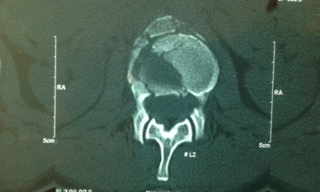

No joke: every day of this trek was a bluebird day. After sorting out meds for various URI (Upper Respiratory Infection) symptoms, we set out for Lukla. About two hours into the trek, I received word that one of our Trekkers fell and had back pain. Jim and I, along with Nima Dorji Sherpa, back-trekked in sixth gear about 20 minutes to find our friend in the excellent care of Deja, our soon-to-be 1st year med student at University of Chicago. Deja was holding c-spine immobilization, and proceeded to present the patient to me in an efficient and organized manner so that we were caught up in 60 seconds. Clearly, Deja took our scenario and lectures on trauma in the backcountry to heart. Our trekker had pain but luckily was completely neurologically intact, in spite of what was likely a 30-ft fall landing on her feet. We had a big debriefing on prevention and management after the fact, but in the heat of the moment, our team of physicians/Trekkers/Sherpas provided top notch care for our friend, facilitating a helicopter rescue in under an hour. The chopper landing and take-off were award-winning. Any photos posted here are with the patient’s permission. In the end, she had a serious injury – a fracture of her low back – but remained completely neurologically intact. The patient’s transfer out of Nepal was delayed about a week because of how long it took the physicians at the CIWEC Clinic in Kathmandu to convince the patient’s rescue insurance (obtained through her credit card) to arrange for a flight out to where she could be evaluated by a spine surgeon. Ultimately, she was transfered to Thailand, had an operation, and was walking 30 days after the initial fall. She has since returned to her job teaching and continues to travel extensively.

L2 Burst Fracture. The lateral cuts showed retropulsion into the spinal canal. There was no spinal cord injury. The patient awlays had a normal nauerological exam.